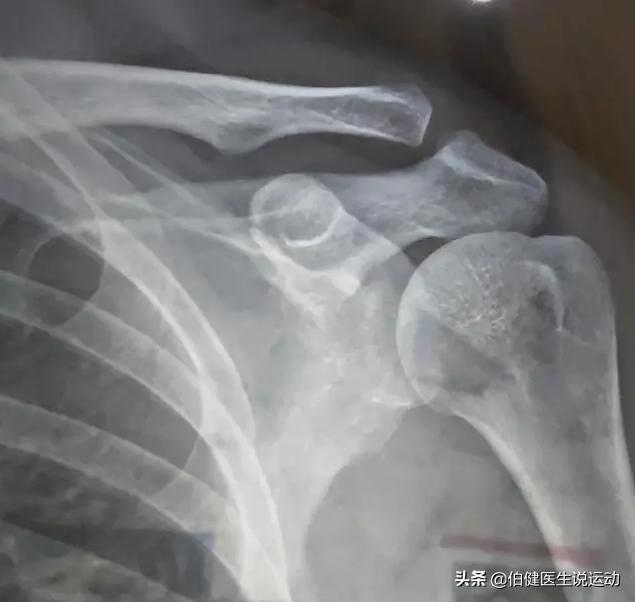

肩锁关节脱位Ⅰ型、Ⅱ型影像学上不明显。容易被忽略。这就需要照特殊的X线照片明确诊断了:

1、让患者两手分别提重物约2.5kg,同时摄双侧肩锁关节正位片进行对比,常可发现患侧锁骨外端与肩峰间距离较健侧增大,全脱位者X线照片,可发现锁骨外侧端与肩端完全分离,向上移位较明显。

2、射线向上成角10°~15°位拍摄X片可更明确肩峰与锁骨远端间距离。

提重物双肩正位片,可发现不明显的脱位

射线向上成角10°~15°正位片